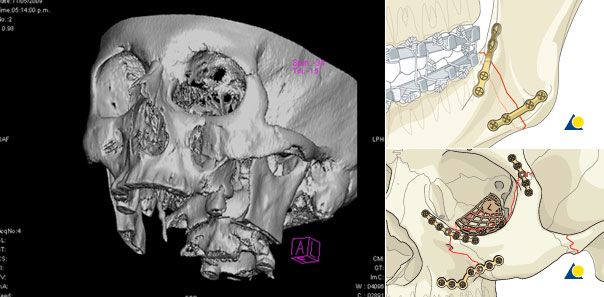

La "traumatología facial" es una parte específica de la traumatología que se dedica al tratamiento de las fracturas mandíbula, maxilar superior, malares, nariz, orbitas, frontal, región etmoidal, etc. Estas requieren un abordaje especializado por parte de un cirujano maxilofacial para evitar secuelas tanto funcionales como estéticas.

Nuestro principio a la hora de tratar este tipo de fracturas se basa en una reconstrucción precisa y minuciosa de las fracturas basándonos en la oclusión real del paciente y exacta relación anatómica; realizando incisiones casi invisibles en la cara. El tratamiento de las fracturas faciales no finaliza tras la intervención, sino que en el postoperatorio aportamos un tratamiento de recuperación mediante fisioterapia y rehabilitación.

La fijación de las fracturas se realiza a través de "miniplacas" de titanio de bajo perfil que nos aseguran un resultado excelente.

La colocación de estas placas se realiza a través de incisiones ocultas o transbucal que permite reconstruir la fractura sin cicatrices en la cara.